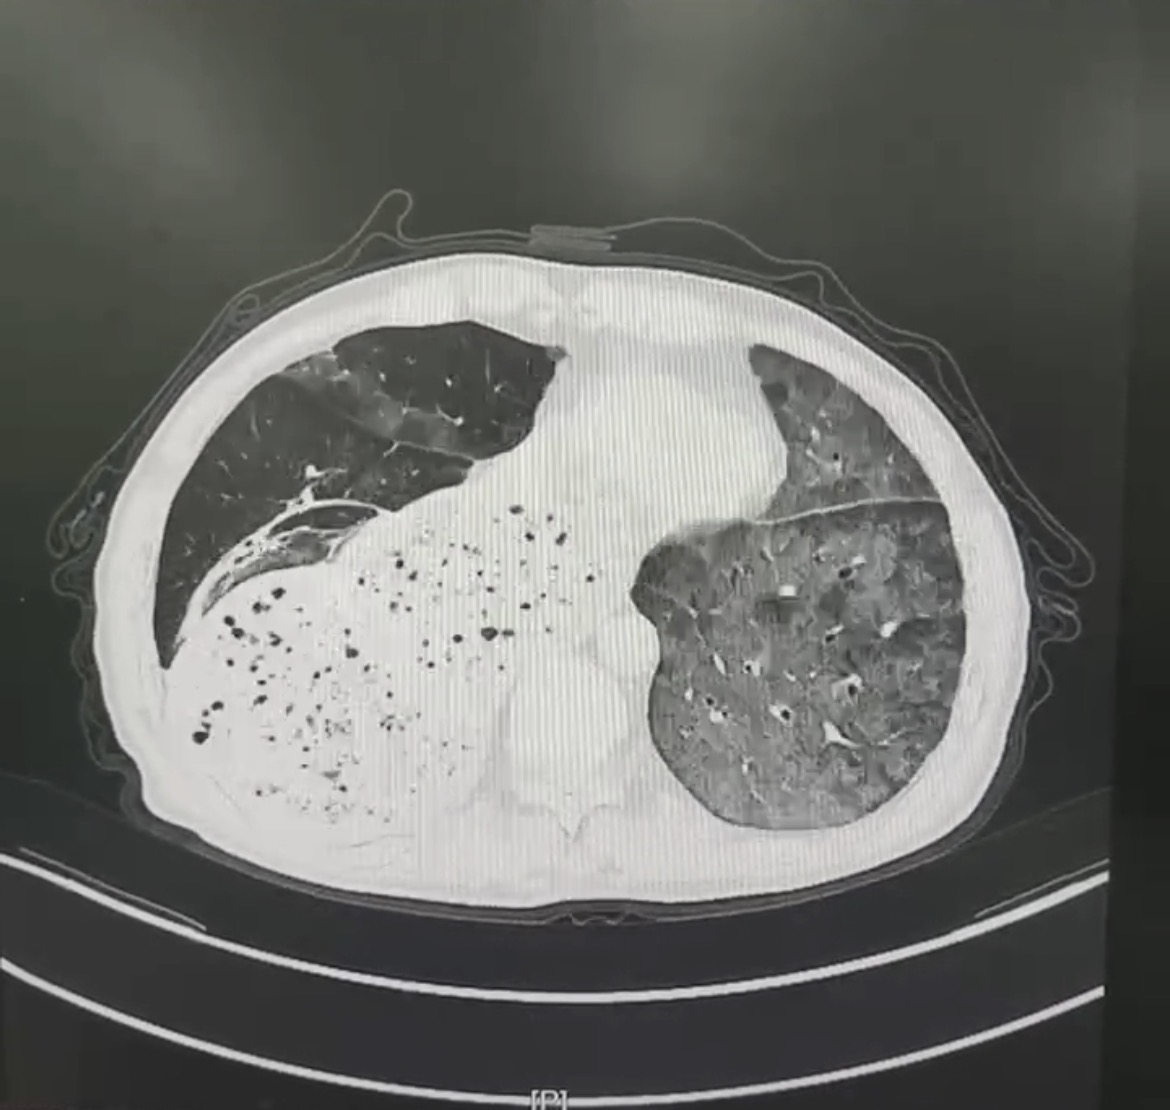

患者赵先生,反复的胸闷、呼吸困难一年有余,每一次呼吸都成为一种负担。随着时间推移,病情逐渐恶化,平静休息时难以缓解,活动后症状加剧。赵先生曾辗转多家医院就诊,然而疾病始终诊断不明,治疗效果不佳,病情时有反复,令患者和家属备受煎熬。近期,患者的病情急转直下,胸闷气急加重,甚至出现呼吸衰竭。门诊胸部CT提示两肺弥漫性渗出病变,紧急收入我院。

胸部CT